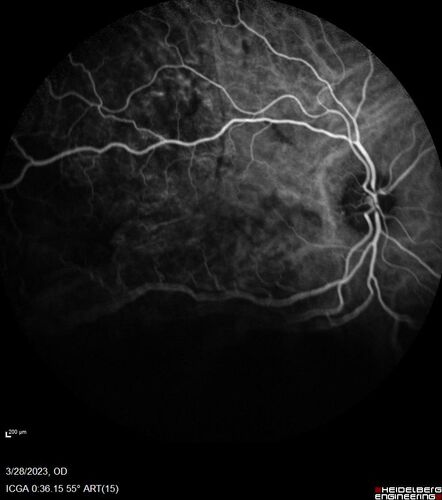

Choroidal Metastatic Breast Cancer with Exudative Detachment

58 year old female presented with 20/200 vision. Had 10 sessions of radiation and tumor shrank. The exudative detachment took almost a year to resolve. The vision improved to 20/40.